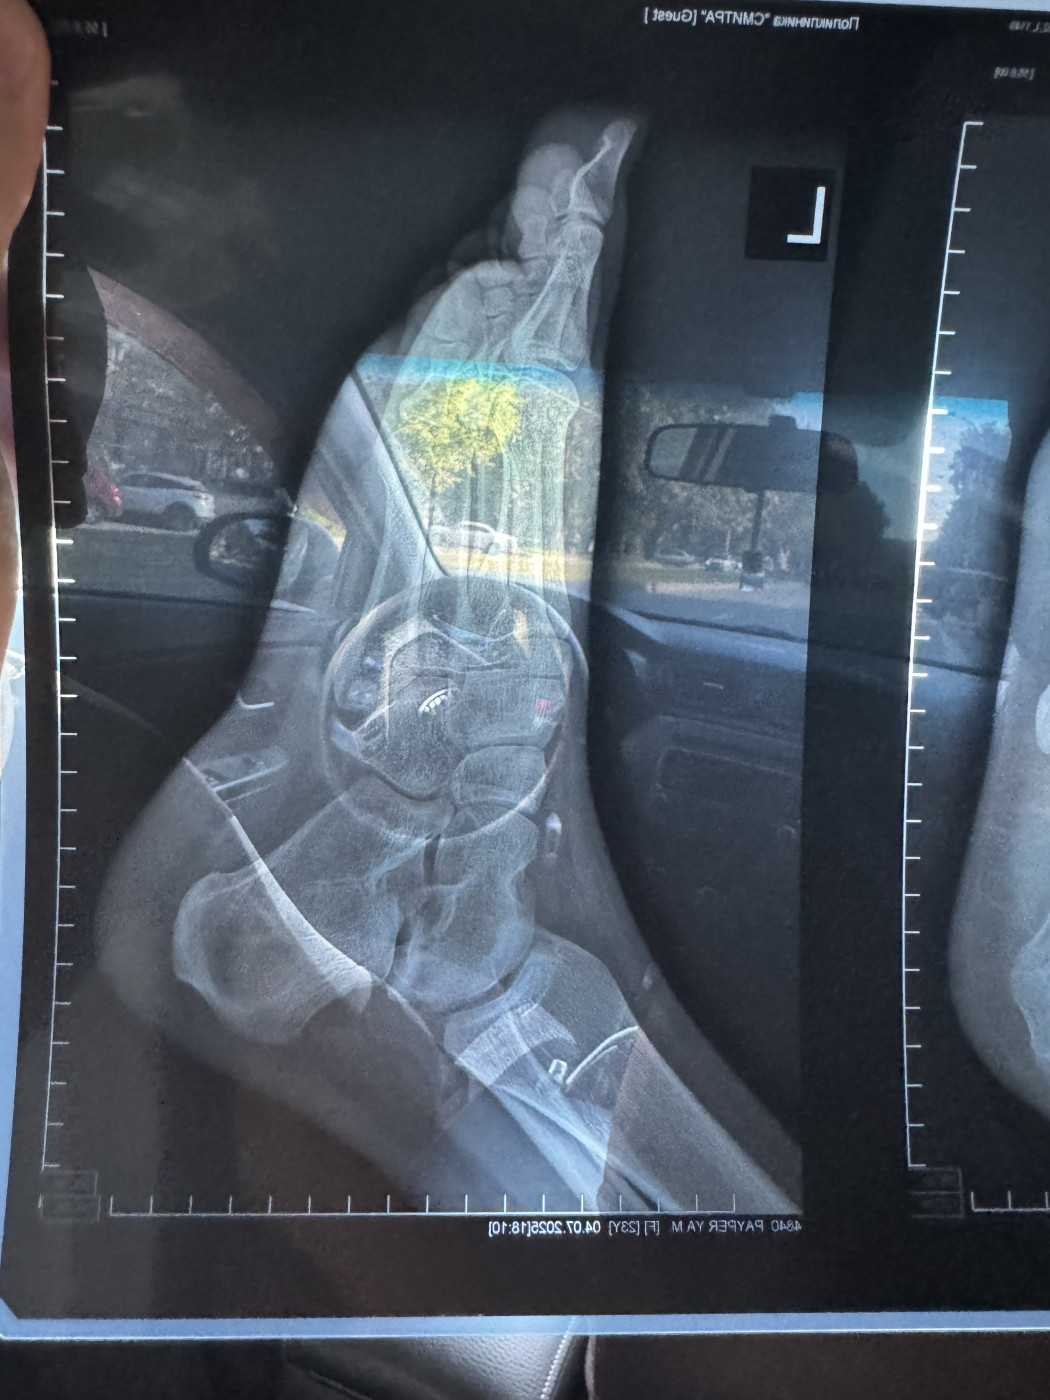

Жмет пластиковый ортезДобрый день! 3 ноября я сломала пятую плюсневую кость на левой ноге, перелом без смещения. Мне наложили гипс. 15 ноября после повторного рентгена (снимок от 15 ноября на фото) мне наложили пластиковый ортез ordect и сказали, что я могу ходить с опорой на пятку. Но этот ортез мне жмет, мизинец очень плотно прижат к другим пальцам. |